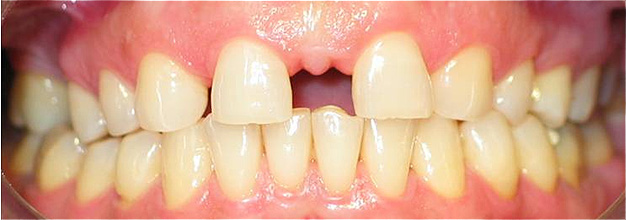

Caso 4 - Agenesia dos incisivos laterais superiores - tratamento ortodôntico para encerramento de diastema e implantes

![]() |